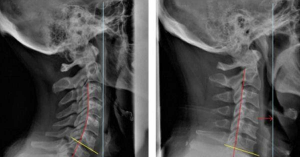

• X-quang: Cho thấy hình ảnh đốt sống, gai xương hoặc khe khớp bị thu hẹp.

X-quang - gai đốt sống cổ

X-quang – gai đốt sống cổ

(Nguồn: Thu Cúc)